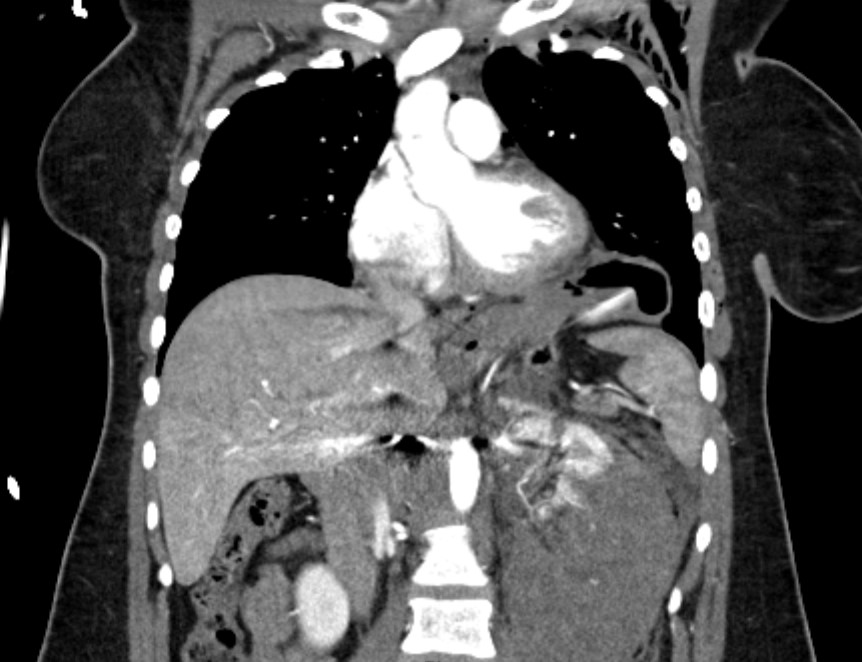

Case Quiz: 31-Year-Old With Multiple Car Crash Injuries

Athanasios Pavlou offers radiographs and CTs to help differentiate your diagnosis.